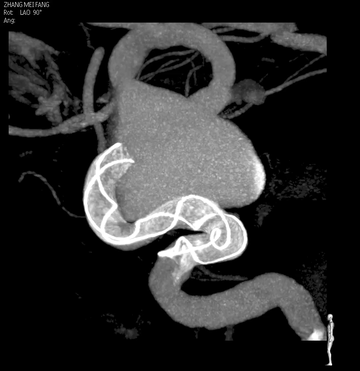

Tubridge Plus Case 4